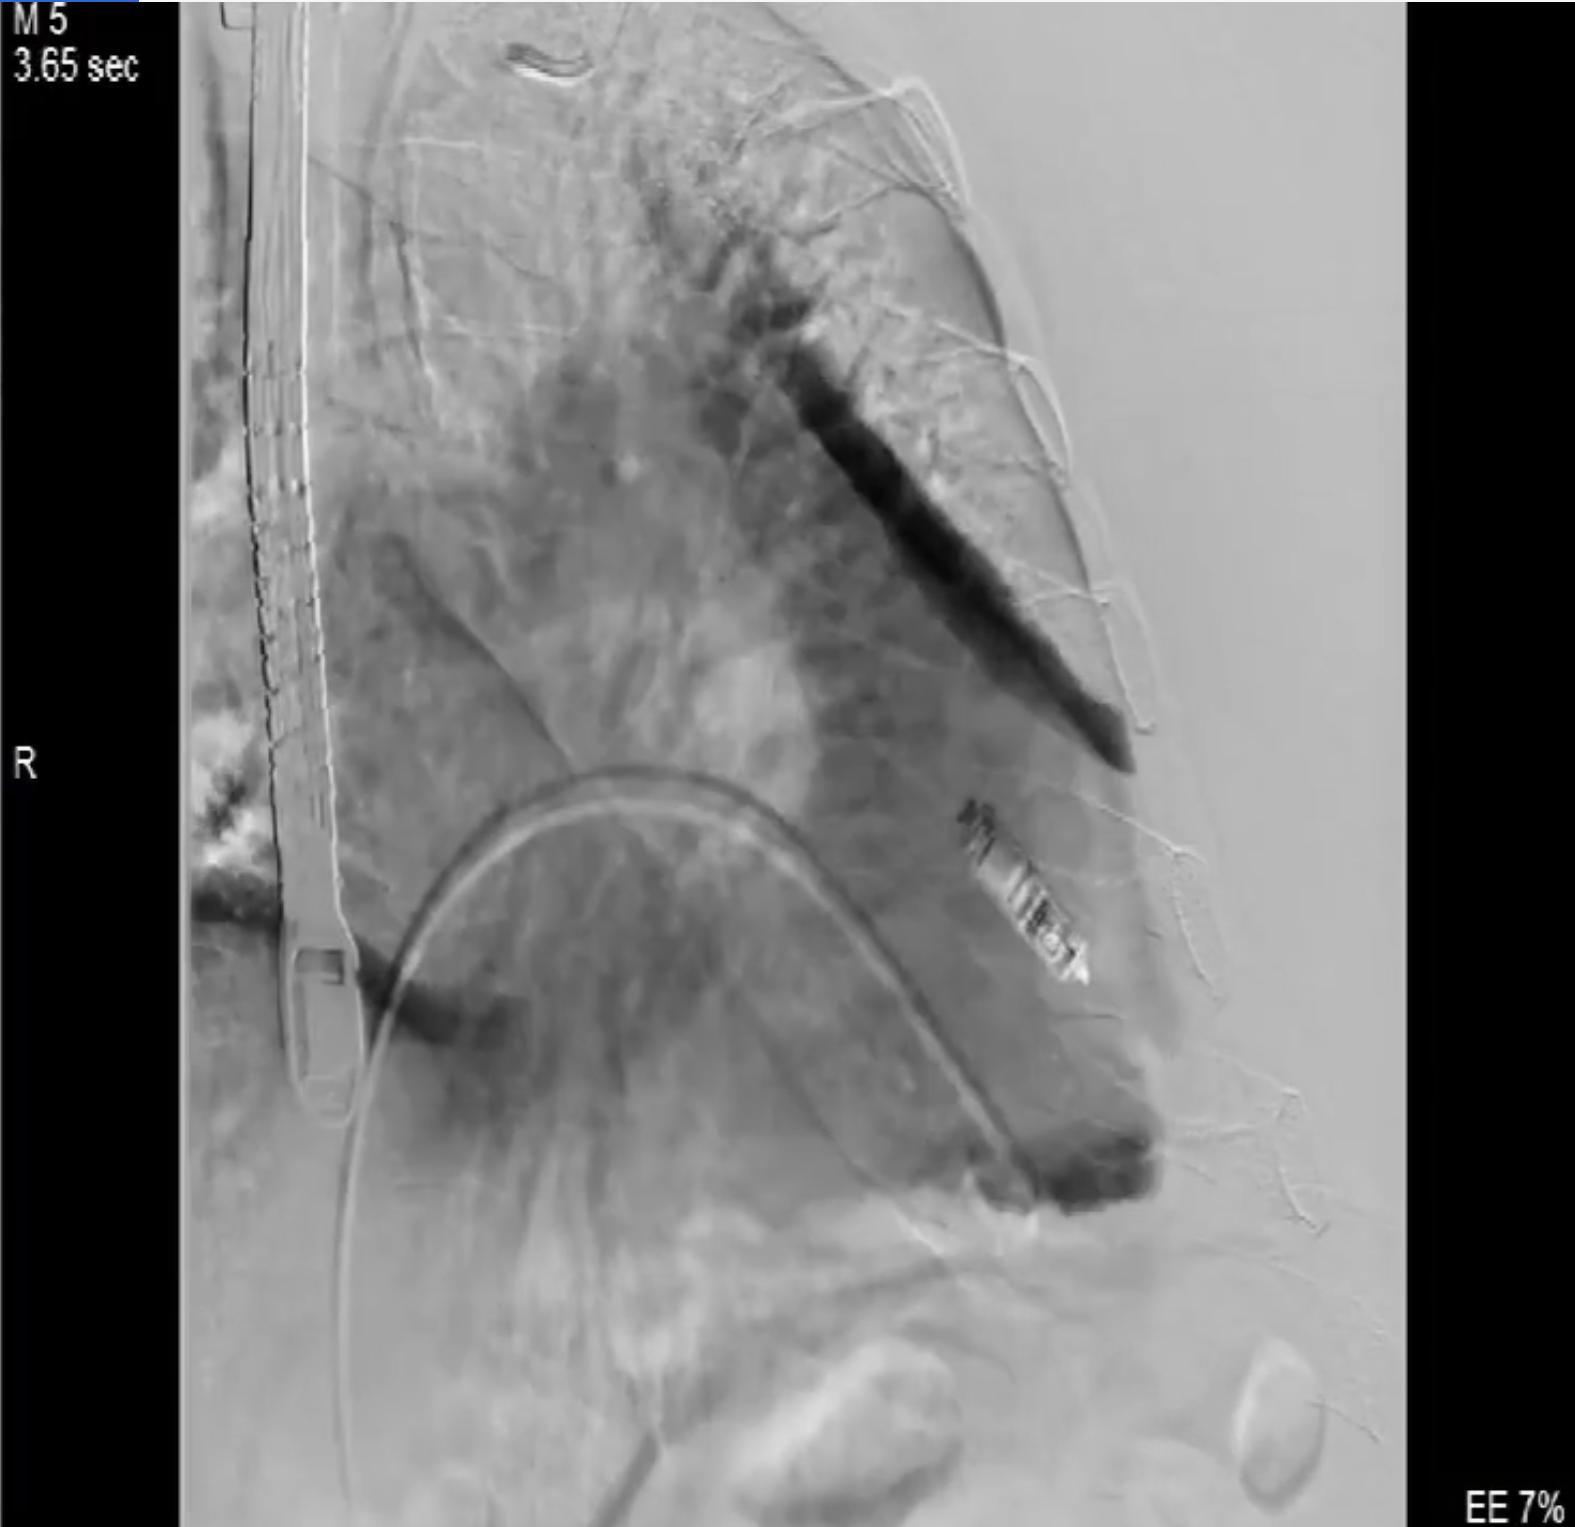

術前DSA造影可見三尖瓣大量返流呈瀑布樣,右室偏間隔側可見無導線起搏器一枚。

本次直播手術中,手術團隊在超聲與DSA等多維影像手段的支持下,精準嫻熟的完成LuX-Valve Plus瓣膜的植入,器械操作時間僅為30分鐘,瓣膜植入后術中即刻三尖瓣返流消失,多普勒超聲下無明顯瓣周漏或中心性返流,肺動脈壓正常,平均跨瓣壓差僅為1mmHg,人工瓣膜運動正常,術后1小時內該患者即安返病房。